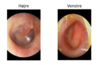

En 27-årig mand har haft kraftige smerter i højre øre siden i går. Kunne ikke sove i nat pga smerterne, trods mange panodil. Har ikke haft øreproblemer tidligere. Objektivt; kraftige smerter når man trækker i øret og trykker på tragus. Vedr otoskopi af højre øre; se foto.

Hvad er den mest sandsynlige diagnose?

- a. Sekretorisk otitis media

- b. Perforatio membrana tympani

- c. Akut otitis media

- d. Otitis eksterna

- e. Cerumen

d. Otitis eksterna

En 3-årig pige har grædt i nat og har taget sig til højre øre. Hun har for tre måneder siden

fået målt flade kurver ved tympanometri. Vedr otoskopi af højre øre; se foto.

Hvad er den mest sandsynlige diagnose?

- a. Kolesteatom

- b. Kronisk otitis media

- c. Sekretorisk otitis media

- d. Akut otitis media

- e. Myringitis bullosa

d. Akut otitis media